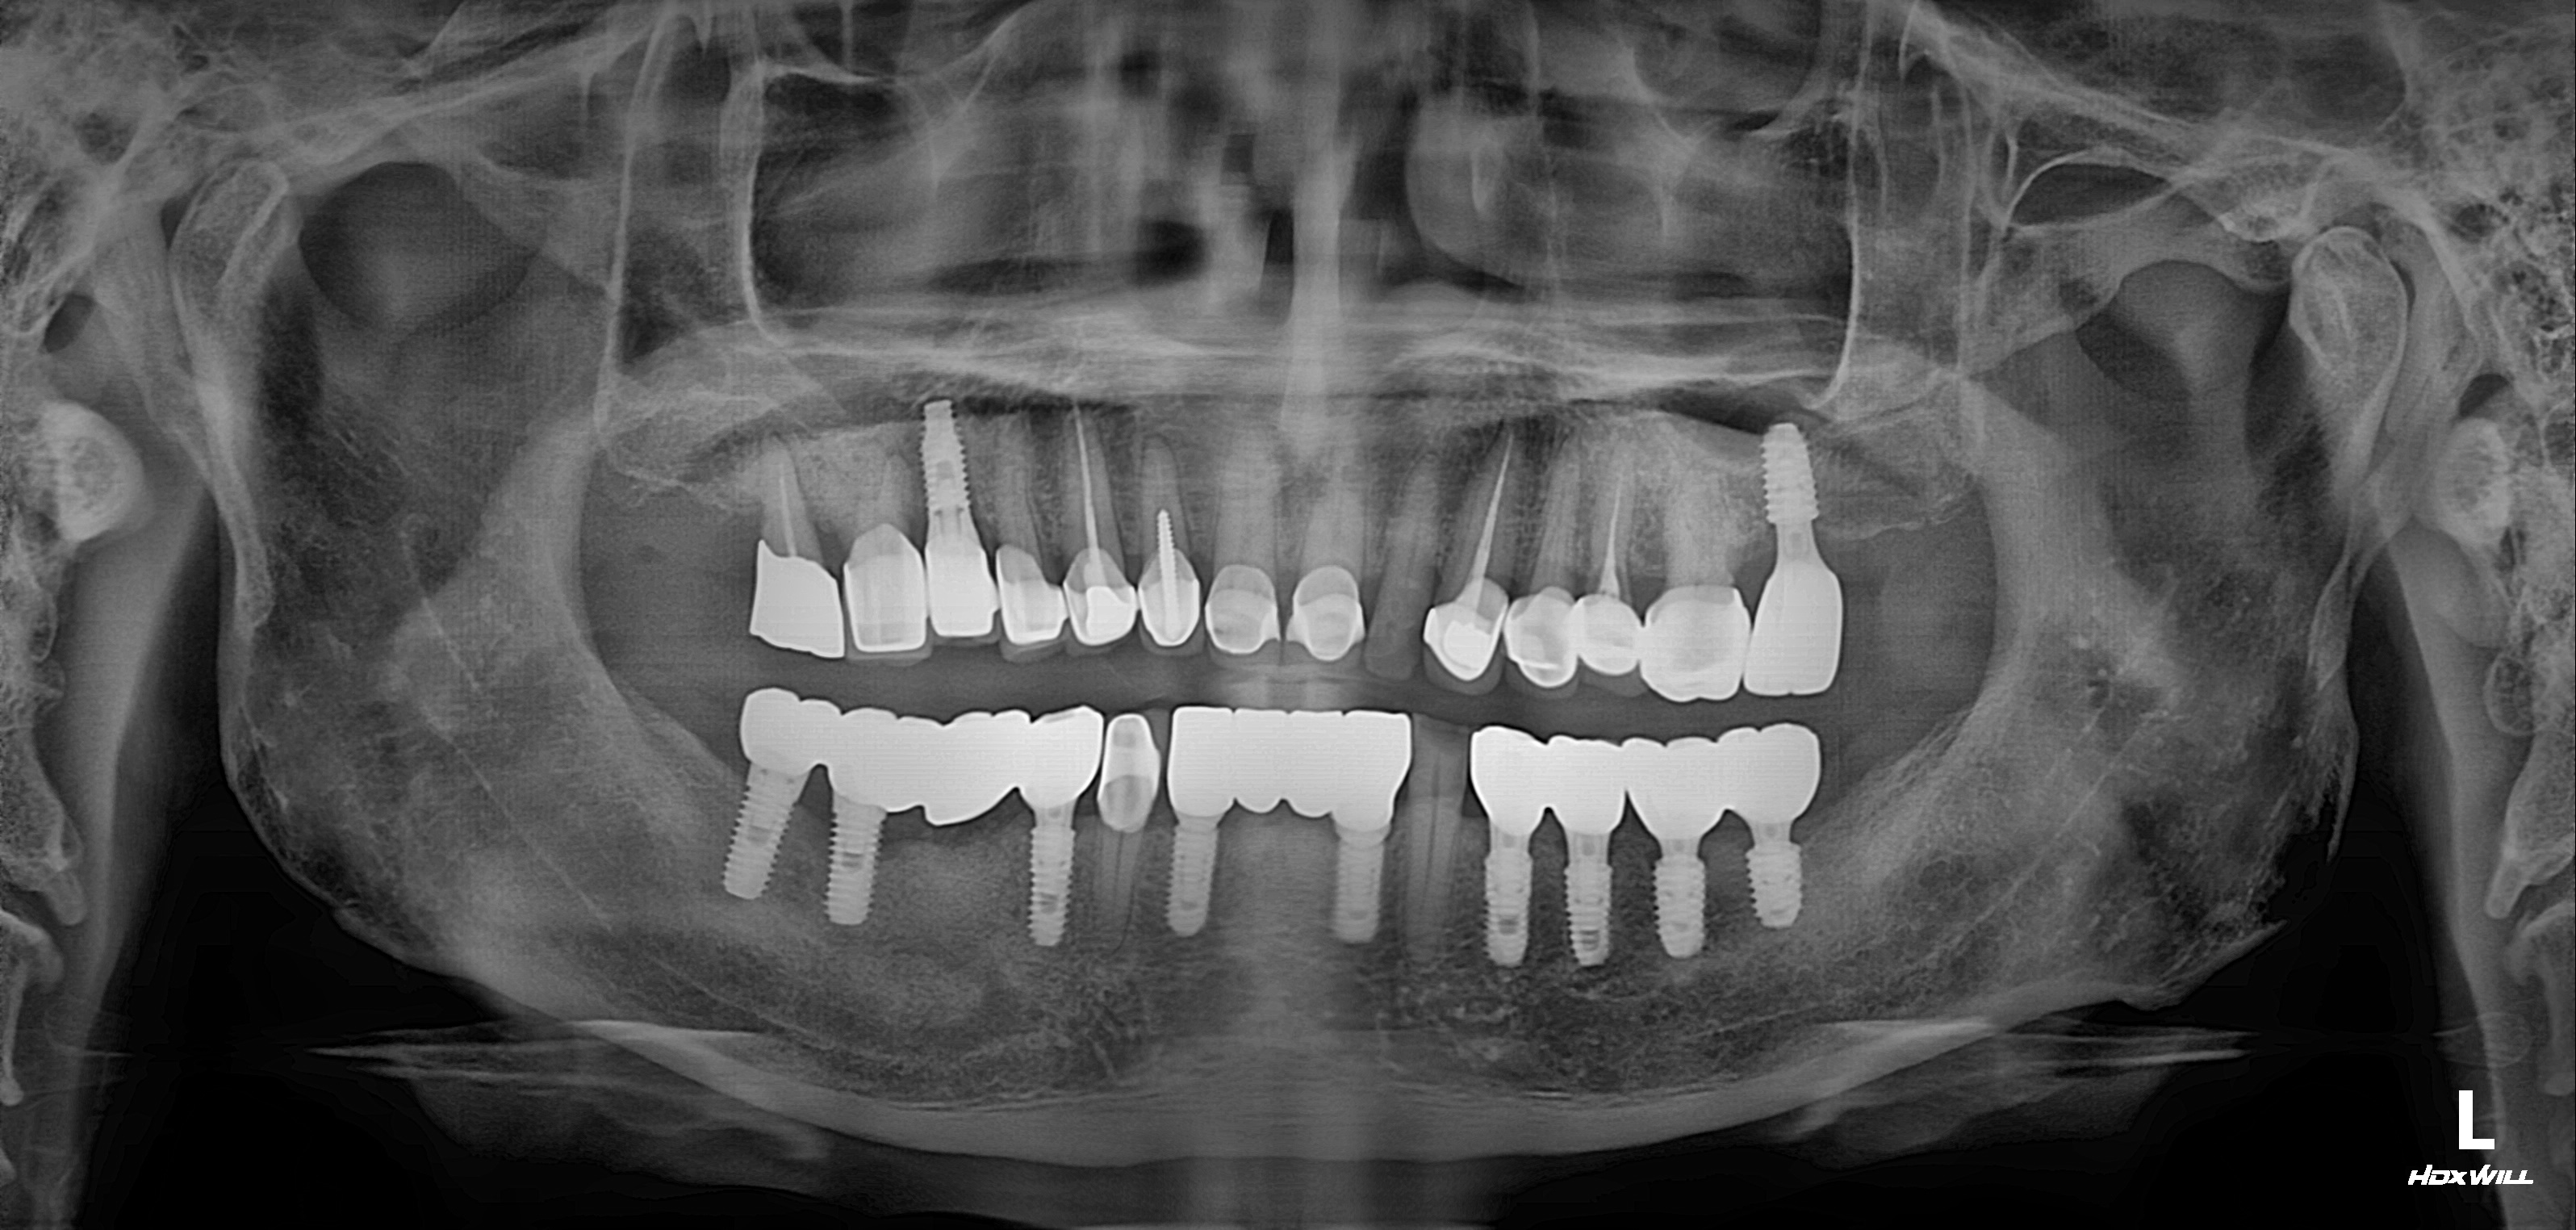

수술 전

수술 후

전악 임플란트 식립사례

전후사진